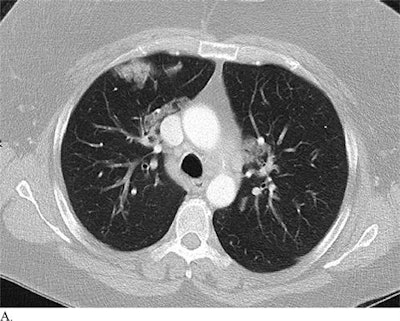

"This low specificity [for CT] may stem from the fact that it is difficult to distinguish COVID-19 findings from findings of other disease on chest CT. ... For example, influenza and COVID-19 both demonstrate ground-glass opacity and consolidation on chest CT," wrote a team of researchers led by Dr. Harrison Bai from Rhode Island Hospital.

The researchers also listed several CT patterns that were much more common in patients with COVID-19 than in those without the disease: ground-glass opacity, peripheral distribution, vascular thickening, fine reticular opacity, and reverse halo sign.